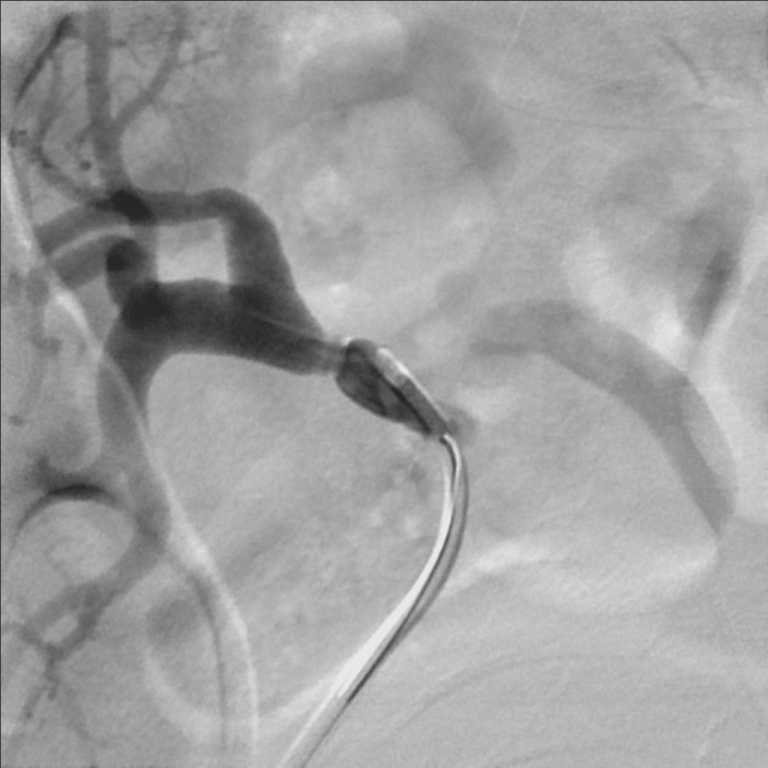

The patient was referred for renal angiography, which revealed a focal web-like stenosis in the mid portion of the transplanted renal artery (Figure 1). A Fractional Flow Reserve (FFR) wire was advanced through the stenosis and a 45 mmHg gradient was noted across the lesion. Subsequently, a 5 × 20 mm RX Viatrac 14 Plus balloon (Abbott Vascular, Inc., CA, US) was crossed and inflated to its nominal pressure (Figure 2). Post-angioplasty (Figure 3), the systolic gradient across the stenosis decreased to 25 mmHg. More aggressive dilatations were not performed because of the proximity of the stenosis to the bifurcation of the renal artery. A decrease in the blood pressure was noted in the recovery room and remained controlled without antihypertensive therapy in the subsequent visits.

Figure 2: A 5 × 20 mm RX Viatrac 14 Plus balloon (Abbott Vascular, Inc., CA, US) is used to cross the lesion and inflated to its nominal pressure. View Figure 2